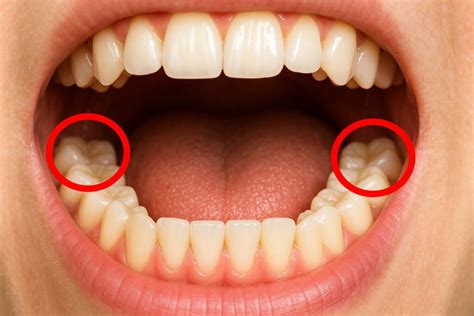

Las muelas de juicio, también conocidas como terceros molares, son los últimos dientes permanentes en salir, generalmente entre los 17 y 25 años. El problema surge cuando no hay suficiente espacio en la boca para que salgan y se desarrollen normalmente, en estos casos es muy probable que sea necesaria su extracción.

Muela del juicio retenida.